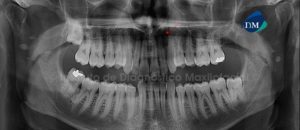

Paciente masculino, 71 años de edad, es referido al Instituto de Diagnóstico Maxilofacial – IDM para evaluación de pieza dentaria 13 por presentar dolor y